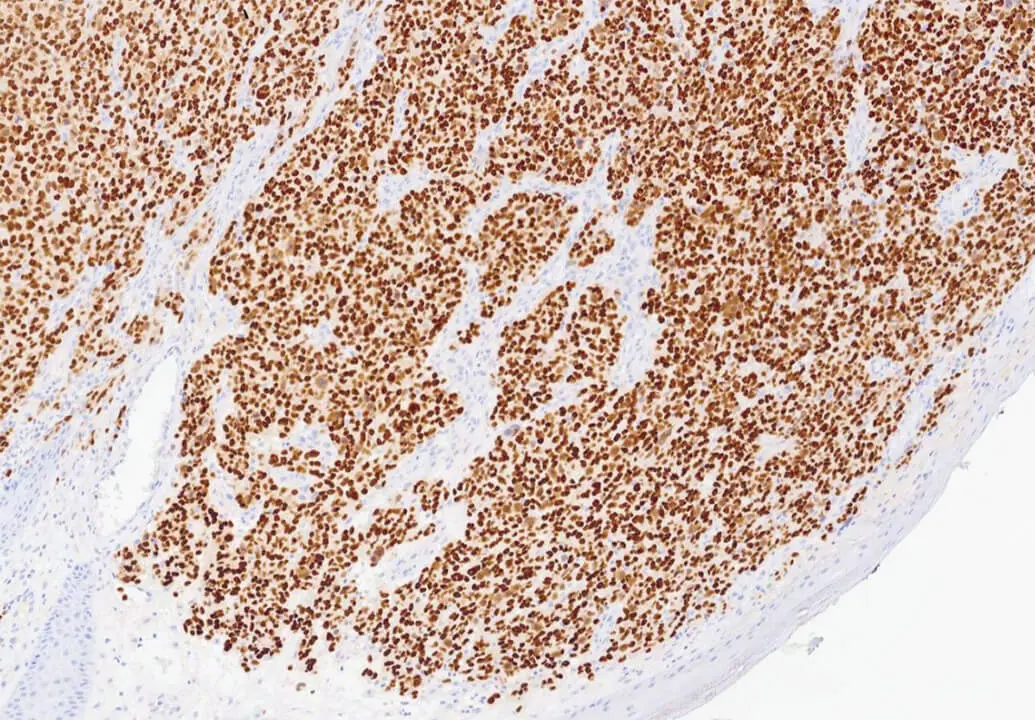

Melanoma: DAB staining of SOX10. Clone SOX10/991.

SOX10 is a nuclear transcription factor in the SOX (SRY Box) family of proteins, that plays an important role in neural crest development among other functions. As such it is expressed in cells of neural crest origin, including melanocytes and Schwann cells. It has been shown to be a sensitive and specific marker to aid in the diagnosis of melanoma, including spindle and desmoplastic subtypes, as well as a specific marker to aid in the differentiation of Malignant Peripheral Nerve Sheath Tumor (MPNST) from synovial sarcoma.

SOX10 is recommended for the detection of specific antigens of interest in normal and neoplastic tissues, as an adjunct to conventional histopathology using non-immunologic histochemical stains.